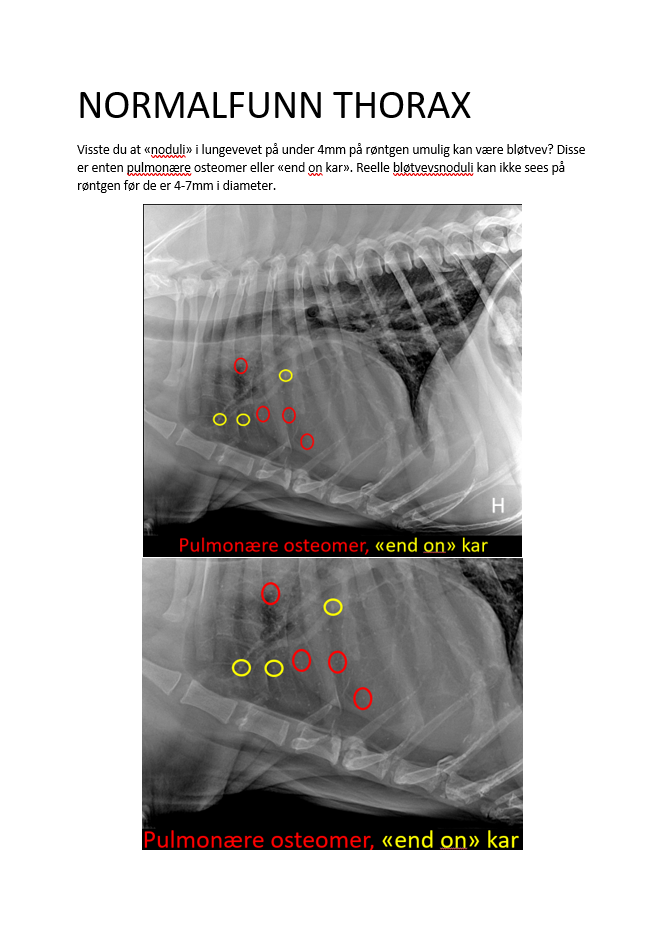

NORMALFUNN THORAX